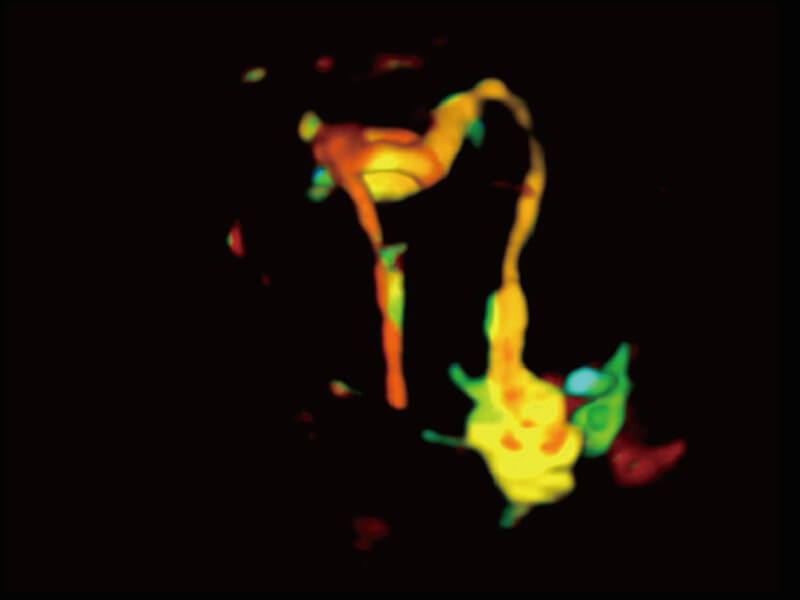

超宽频带技术,为容积成像带来优质的二维图像基础,为您呈现丰富的结构细节,栩栩如生地展示宝宝的宫内形态以及各种组织的立体结构。